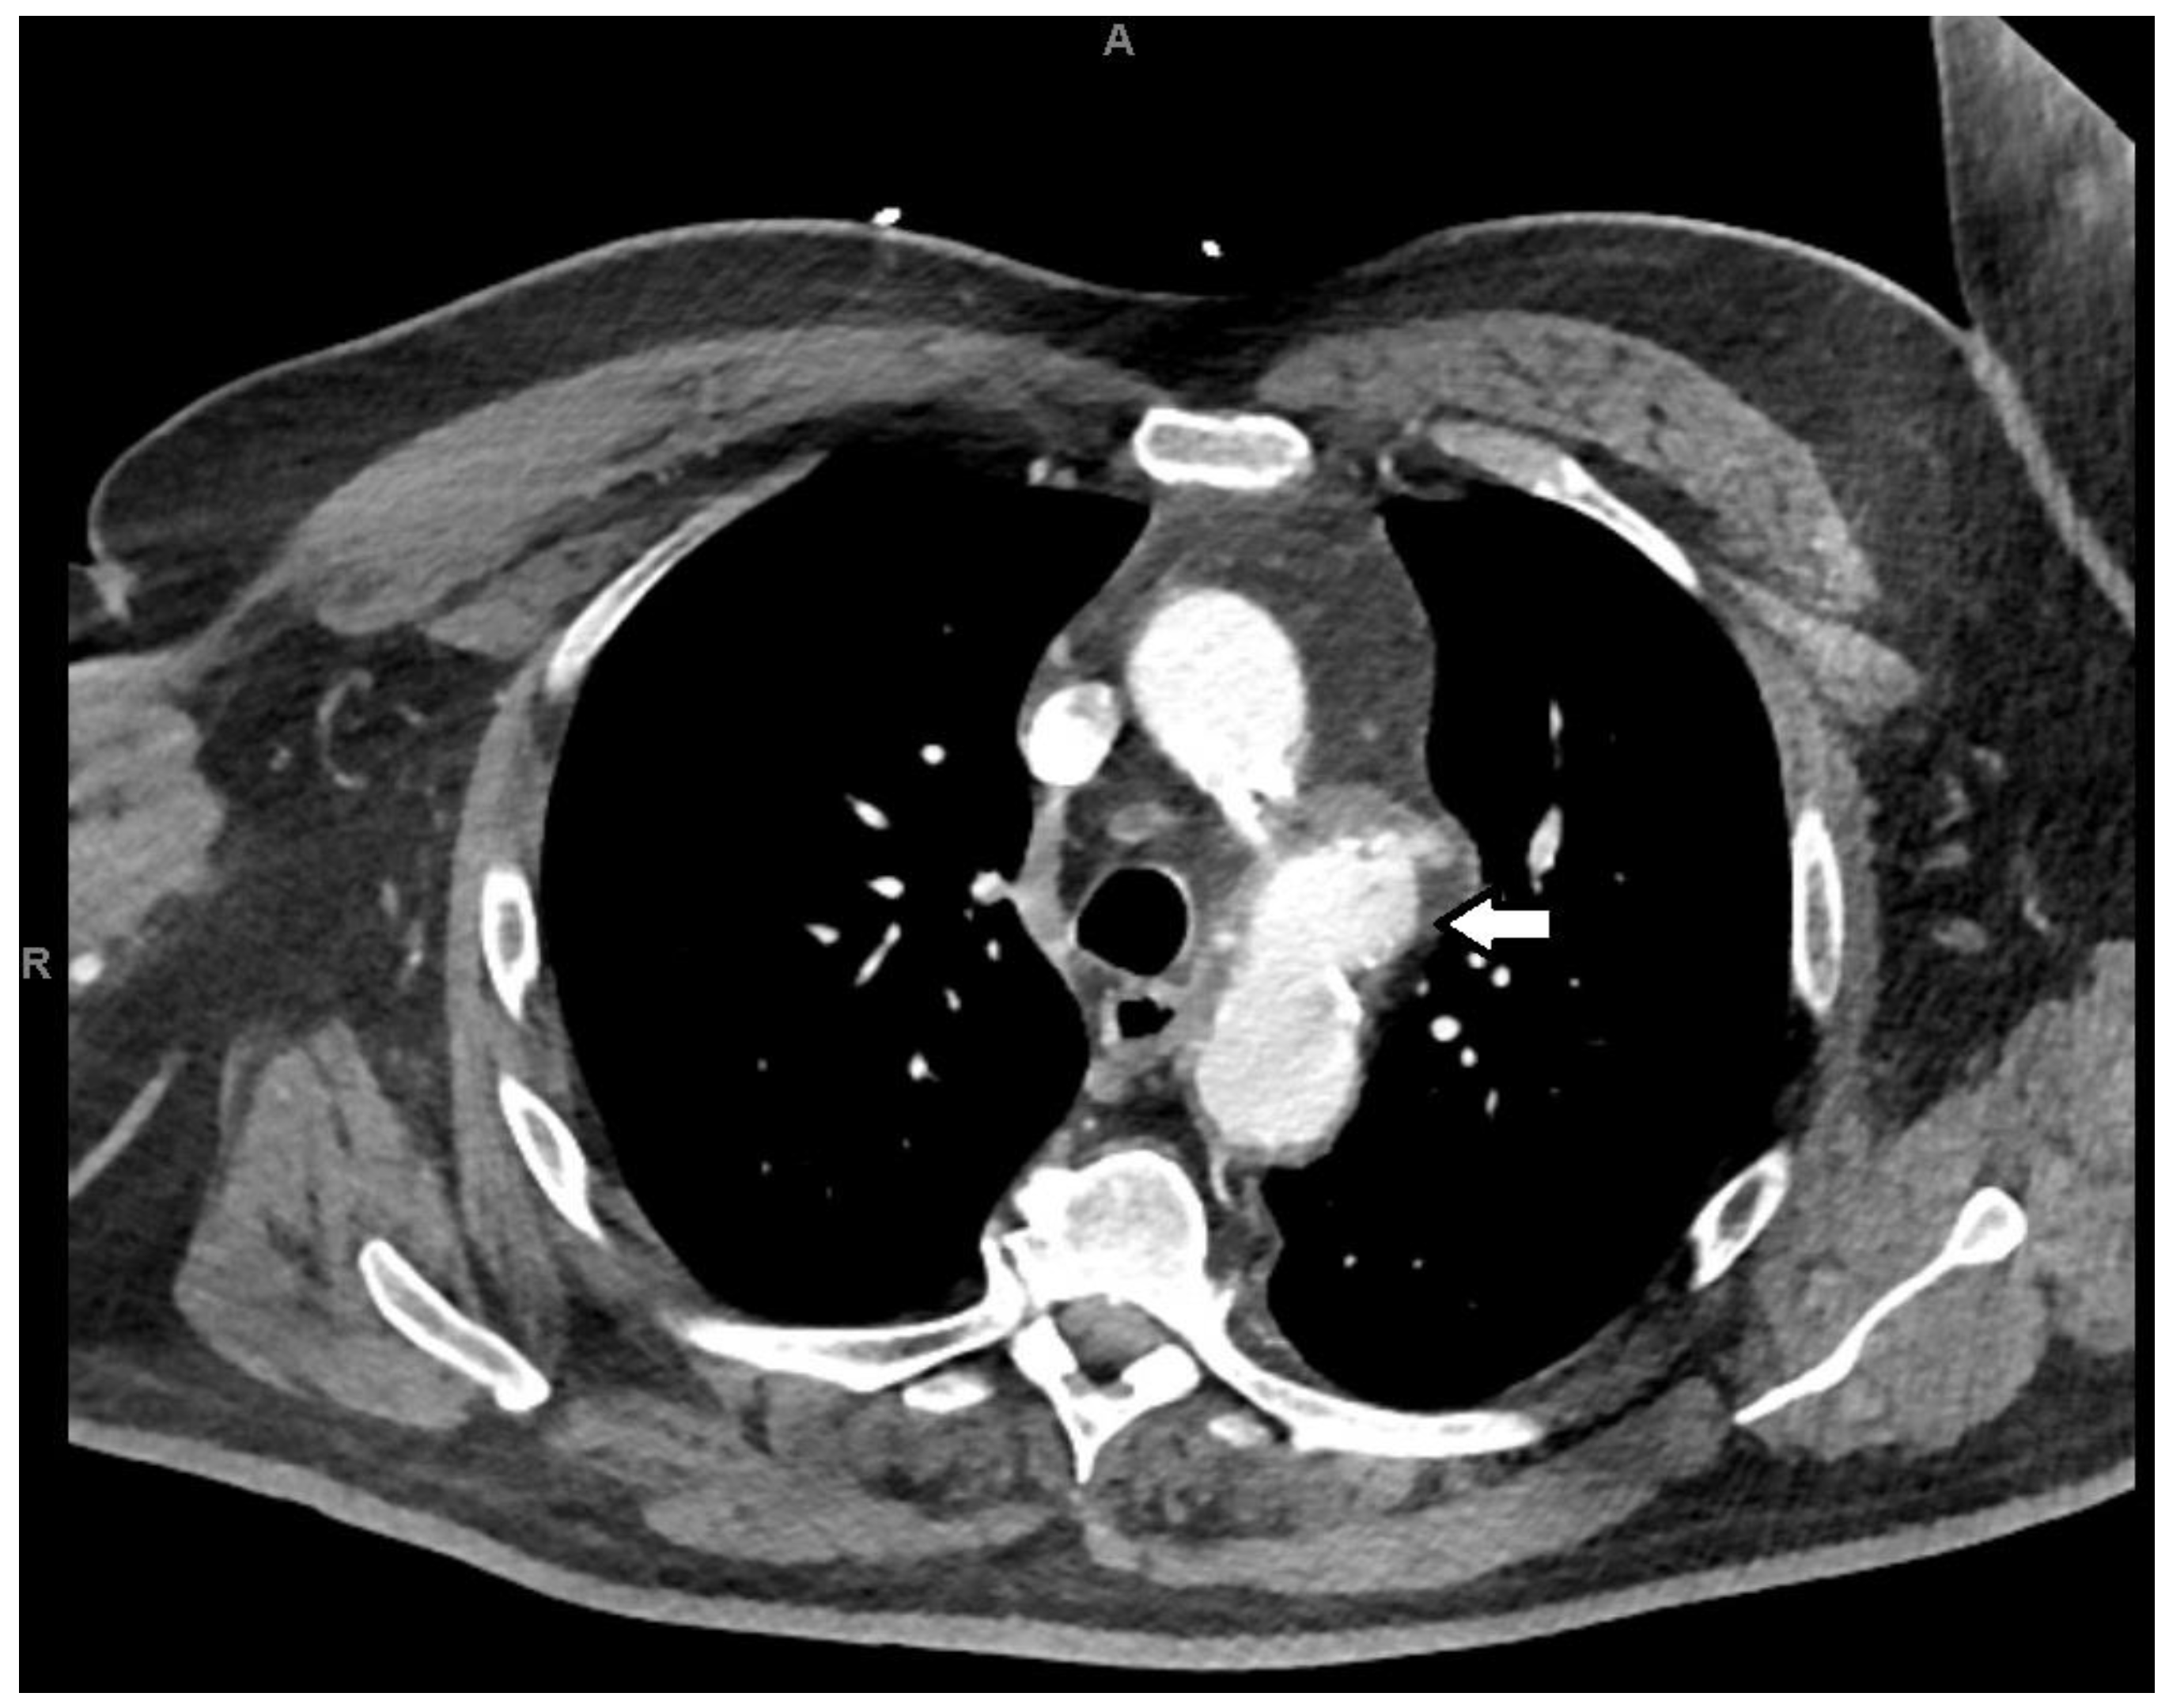

2. Case Presentation